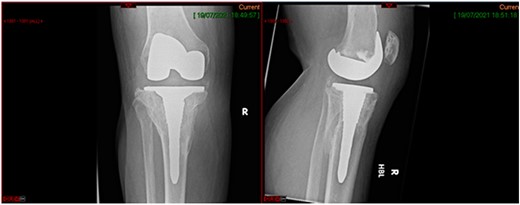

A 68-year-old gentleman who was diagnosed with a Schatzker type VI fracture having fallen 3 m from a ladder (Figs 1 and 2). The injury was closed and neurovascularly intact. The patient was monitored for signs of compartment syndrome. He rapidly developed significant fracture blisters that persisted for over 2 weeks despite regular dressing care. He was deemed too high risk for acute operative intervention because of a high risk of wound complications. Following a multidisciplinary team discussion, he was managed in a cast then a knee brace, mobilising non weight bearing for 12 weeks, at which point the fracture was seen to be healing in a valgus malalignment. The patient was allowed to partially weight bear and received physiotherapy. He was reviewed regularly until fracture had united (Fig. 3). At 8 months post-injury, the patient underwent total knee arthroplasty utilizing a Depuy Synthes (Warsaw, In) PFC Sigma TC3 tibial metaphyseal sleeve and stem, and femoral component without sleeve or stem (Fig. 4). The patient was reviewed post-operatively in clinic at 6 months, the wound had fully healed and the range of motion was 0°–120°. The patient’s pain was significantly reduced, and they were independently mobile. They were kept under annual review and seen at 5 years post-operatively with an Oxford Knee score of 35; the patient used no walking aids and was pain free at rest or during normal walking, with the radiograph demonstrating good osseointegration. The latest follow-up at 8 years revealed no radiographical change in implant (Fig. 5).